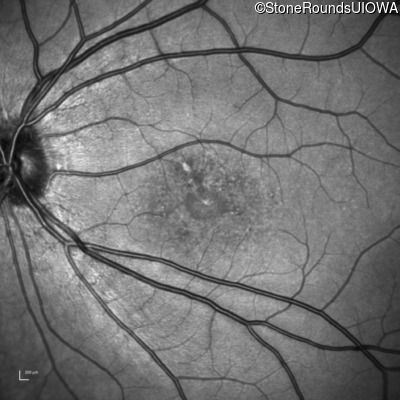

Infrared Fundus Photograph - Right - 20/160 -1 sc

Exemplar

Infrared Fundus Photograph - Left - 20/125 -2 sc